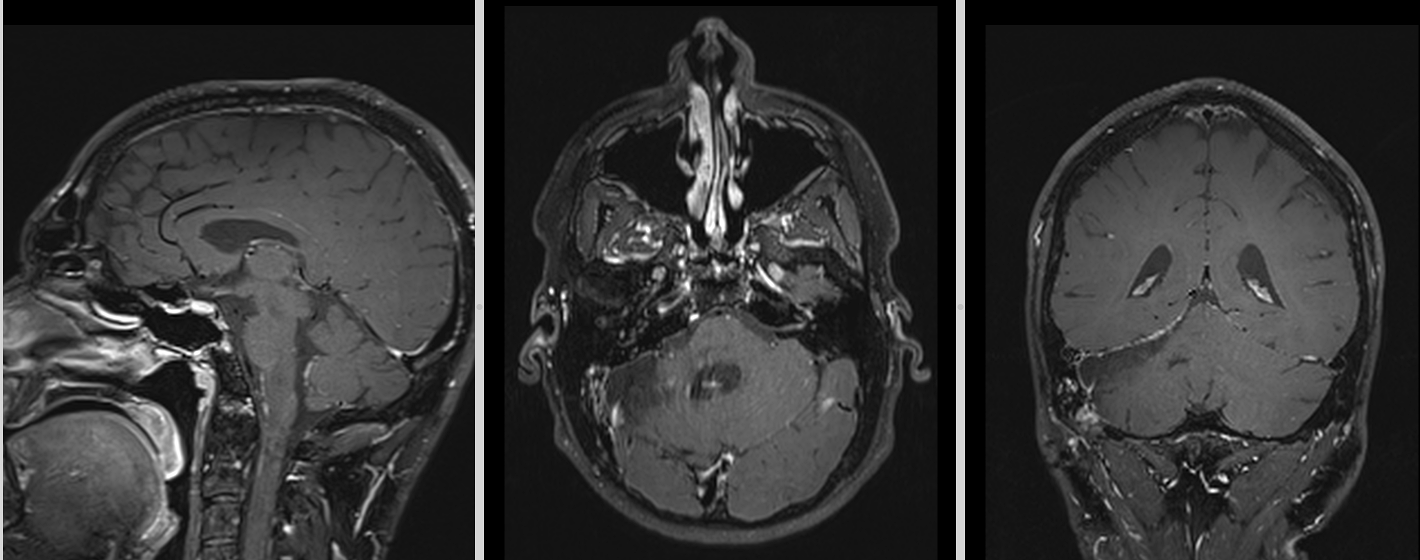

RMN cerebral

Este investigația de elecție. Meduloblastomul apare de obicei ca:

- leziune solidă, bine delimitată sau infiltrativă

- hipointensă T1, hiperintensă T2

- captare intensă de contrast

- posibilă restricție de difuzie (densitate celulară mare)

La adult, localizarea în emisfera cerebeloasă poate duce la confuzie cu alte tumori (metastaze, hemangioblastom, astrocitom).